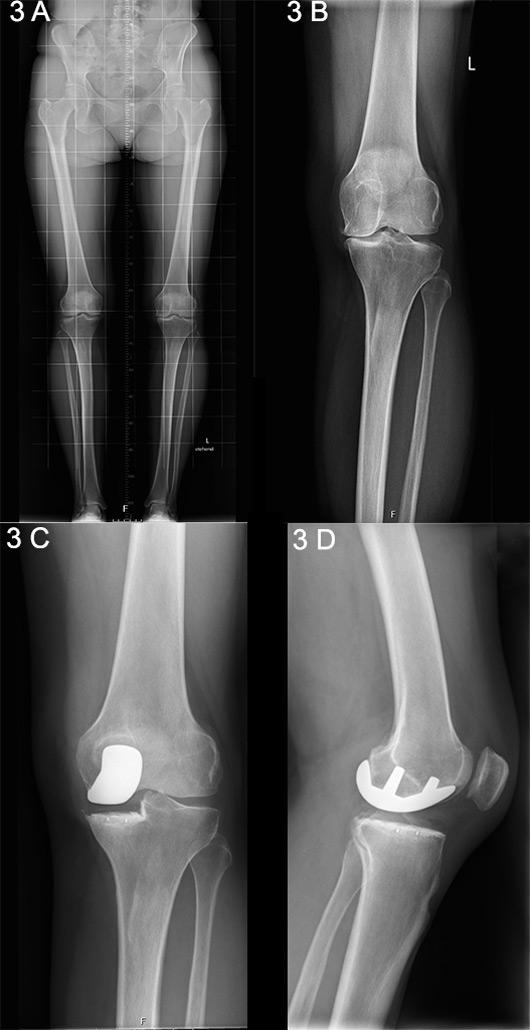

Figure 3

A. Long-standing X-ray showing unicompartmental medial knee osteoarthritis. B. Anteroposterior X-ray showing unicompartmental medial knee osteoarthritis. C. Postoperative anteroposterior X-ray following unicondylar knee arthroplasty (UKA). D. Lateral X-ray following UKA.

Unicompartmental, or unicondylar, knee arthroplasty (UKA) is the preferred choice when the intention is to preserve the intrinsic joint stabilising structures, as well as healthy joint compartments [23] (fig. 3 A‒D) [24]. The general indication for consideration of a UKA procedure is based an isolated involvement of either the lateral or medial tibiofemoral compartment, identified upon clinical and radiographic examination [25, 26]. Silent preoperative radiographic signs of patellofemoral joint disease can be ignored and are not considered a contraindication for UKA [27, 28]. There is only evidence to suggest that, despite a good outcome, patients with lateral patellofemoral OA receiving medial UKA have slightly inferior results than those without, as has been reported by the Oxford Group [29].